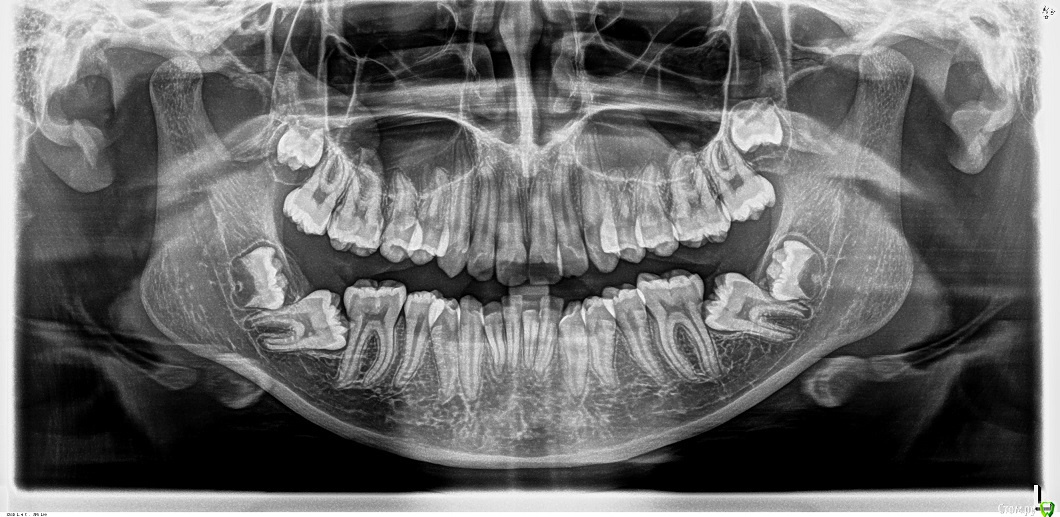

Доброго дня! Дочке 13 лет, есть скученность зубов на НЧ. Запланировали установку брекетов. Сделали снимок, там оказалось все грустно. Теперь веду поиск ортодонта, который готов с этим бороться. Мнения оказались очень разные, некоторые сразу говорят, что браться за это не будут, были даже предложения оставить как есть http://stomforum.ru/images/smilies/icon_e_biggrin.gif. Предлагали удалять 7ки и ждать пока на их место приплывут 8ки. Были предложения удалить зачатки 8к и поднять 7ки, но вот как поднять - вопрос сложный. Очень боюсь выбрать неправильный путь, не хочется мучить ребенка годами безрезультатно. Подскажите, пожалуйста, уважаемые ортодонты, какое Вы выбрали бы решение в сложившейся ситуации?

1. поднять прикус (хоть бы и на плстинке с накусочной площадкой)

2.  открыть зуб и приклеить кнопку.

3. подождать. шанс есть.

4.  если не поможет, можно удалить 8ки и дать тягу на 7-ки (специальные пружины)